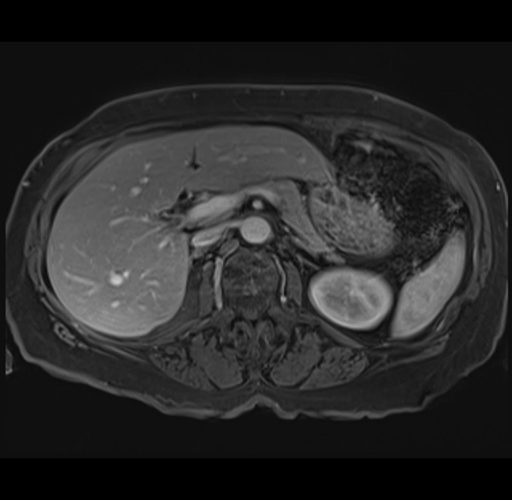

MRI T1